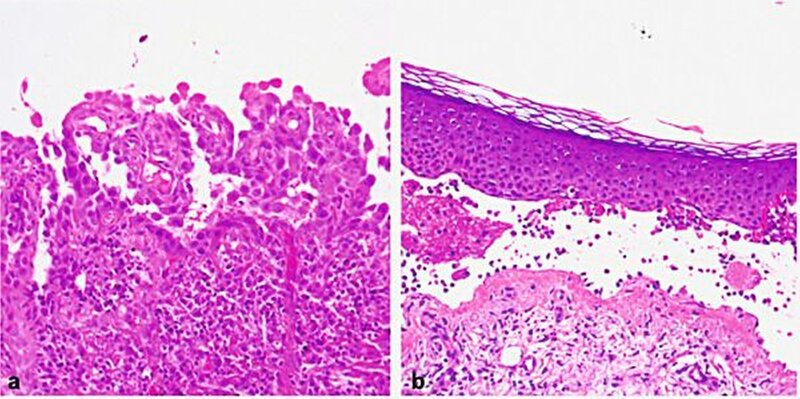

Durch die histologische Untersuchung einer läsionalen Probebiopsie kann man die Ebene der Spaltbildung identifizieren. Die histologische Untersuchung erfolgt mittels einfacher Hämatoxylin-Eosin (HE)-Färbung. Die Pemphiguserkrankungen zeigen eine intraepidermale Spaltbildung und Akantholyse (Abbildung 7a), während die Pemphigoiderkrankungen eine subepidermale Spaltbildung (Abbildung 7b) aufweisen. Eine sichere Differenzierung zwischen den verschiedenen Pemphigoiderkrankungen ist allein anhand der histopathologischen Untersuchung nicht möglich [Schmidt und Zillikens, 2016]. Die Histologie ist vor allem dann hilfreich, wenn die direkte IF sowie die serologische Untersuchung negativ sind, eine bullöse AID daher nicht vorliegt und Differenzialdiagnosen erwogen werden müssen (siehe unten).